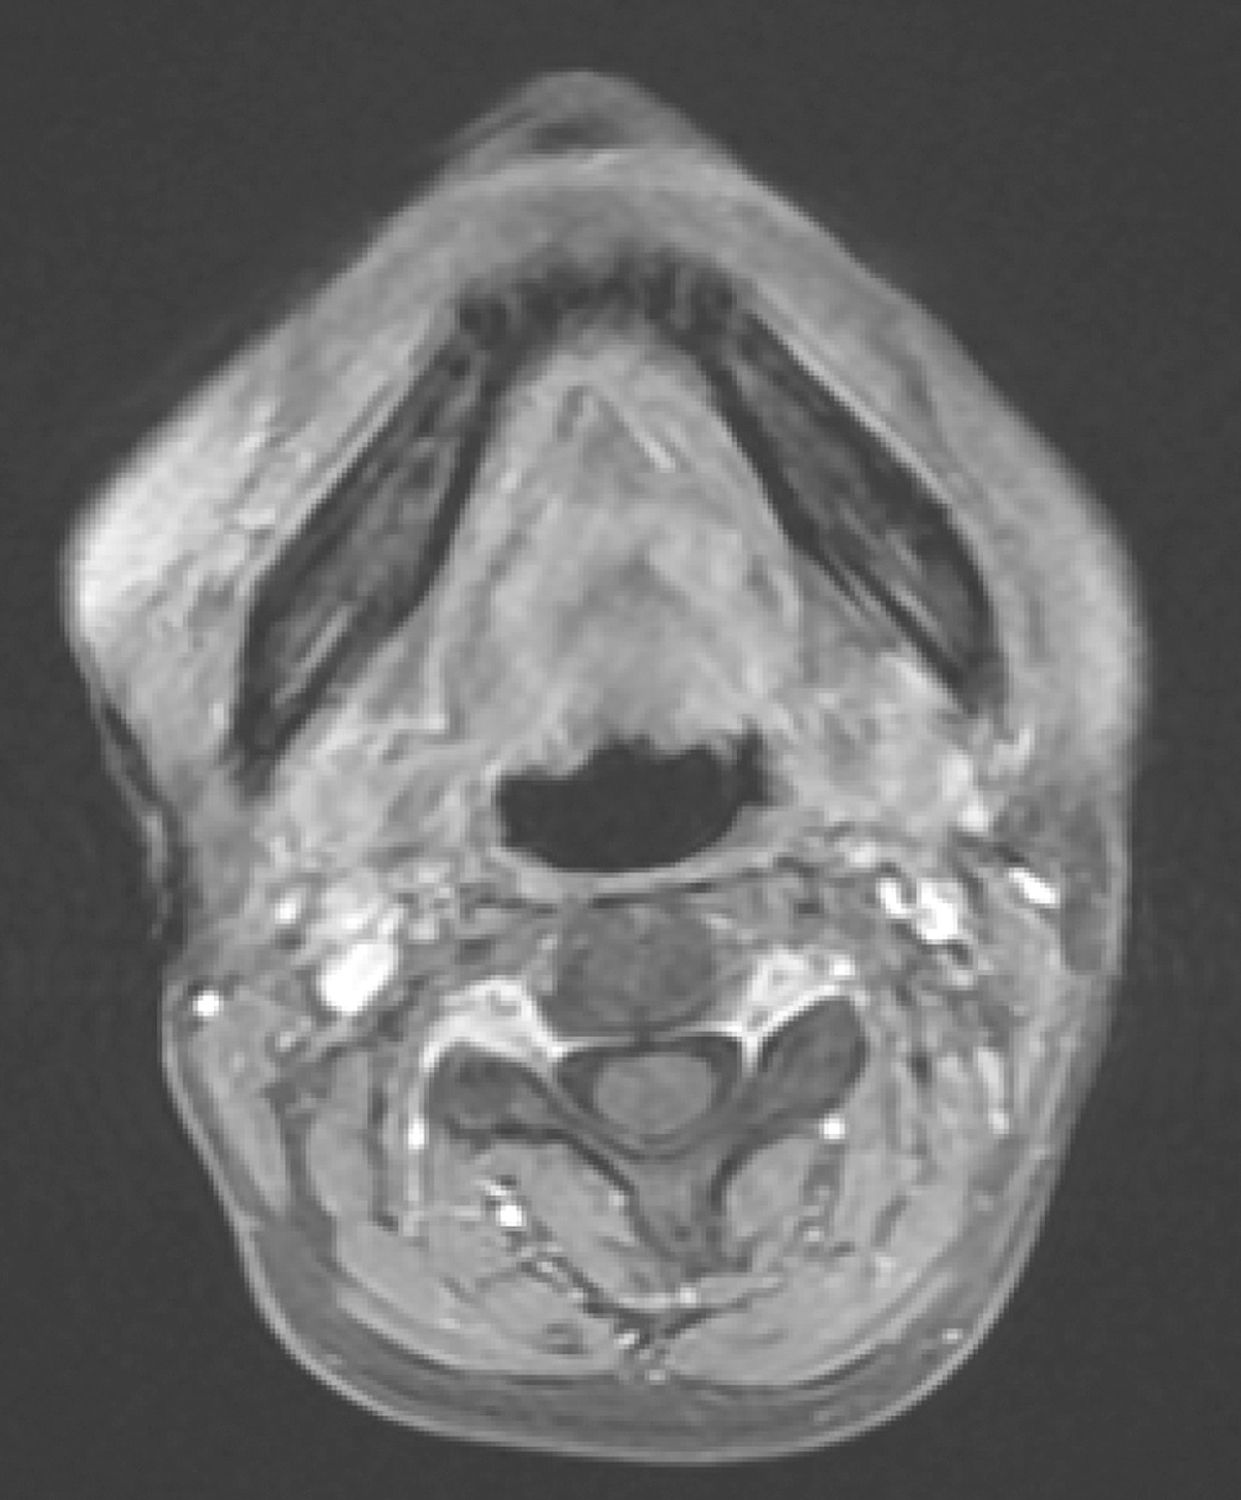

5.2012年10月19日口咽MR平扫检查

“舌部肿物”,与2011年12月28日MR图像:①舌根及口底肿物,大小约2.6cm×2.3cm×2.3cm,同前大致相仿,分叶状,边界不清楚,T1WI呈稍低信号,T2WI等信号,增强扫描不均匀环形强化。口咽左侧壁软组织稍增厚,同前相仿(图3)。②扫描范围内双侧颈深组多个淋巴结,大者约0.6cm,同前大致相仿。③左侧舌肌萎缩。喉部未见明确异常。

图3口腔MRI示舌根及口底肿物,颈深组多个淋巴结,左侧舌肌萎缩